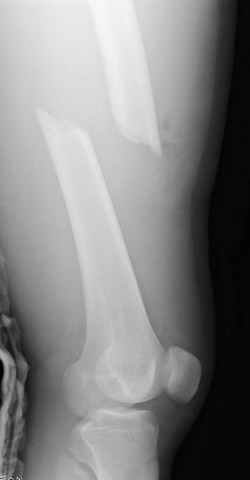

33 yo male motocross rider crashed after a jump sustaining isolated bilateral femur fxs, R side with a basicervical femoral neck and ipsilateral mid-distal 1/3 shaft, L side with a subtroch/prox 1/3 femur fx. Pt was HD stable, no LOC, GCS - 15, No other injuries, spines cleared.

Sequence ­ Right neck, right shaft, then left shaft.

Implants ­ plenty of opinions exist for the right side...some would use neck screws anteriorly after reduction, then with a slender reamed locked nail

pushed in behind the neck screws for the shaft... some will advocate a recon nail for both...some will use a sliding screw for the neck then a retrograde shaft nail...some would use the sliding neck screw and a shaft plate also...lots of options.

I prefer excellent neck reduction either closed or open, screws high and low anteriorly for it, then a frail locked nail slipped in behind the neck screws for the shaft.

The left shaft fracture should accommodate an antegrade reamed locked nail after reduction, unless I¹ve missed some detail on the films as shown.

Chip Routt listed all main options. The right proximal fracture looks closer to trochanteric. Most elegant solution would be to fix all with a single implant with minimal incisions. Long Gamma nail or any other reconstruction or proximal type nails are suitable. Technically less demanding wiuld be temporary neck pinning as is, retrograde nailing of the shaft, then final reduction and fixation of the trochanteric fracture as isolated, by DHS with 2 holes plate. Good luck.